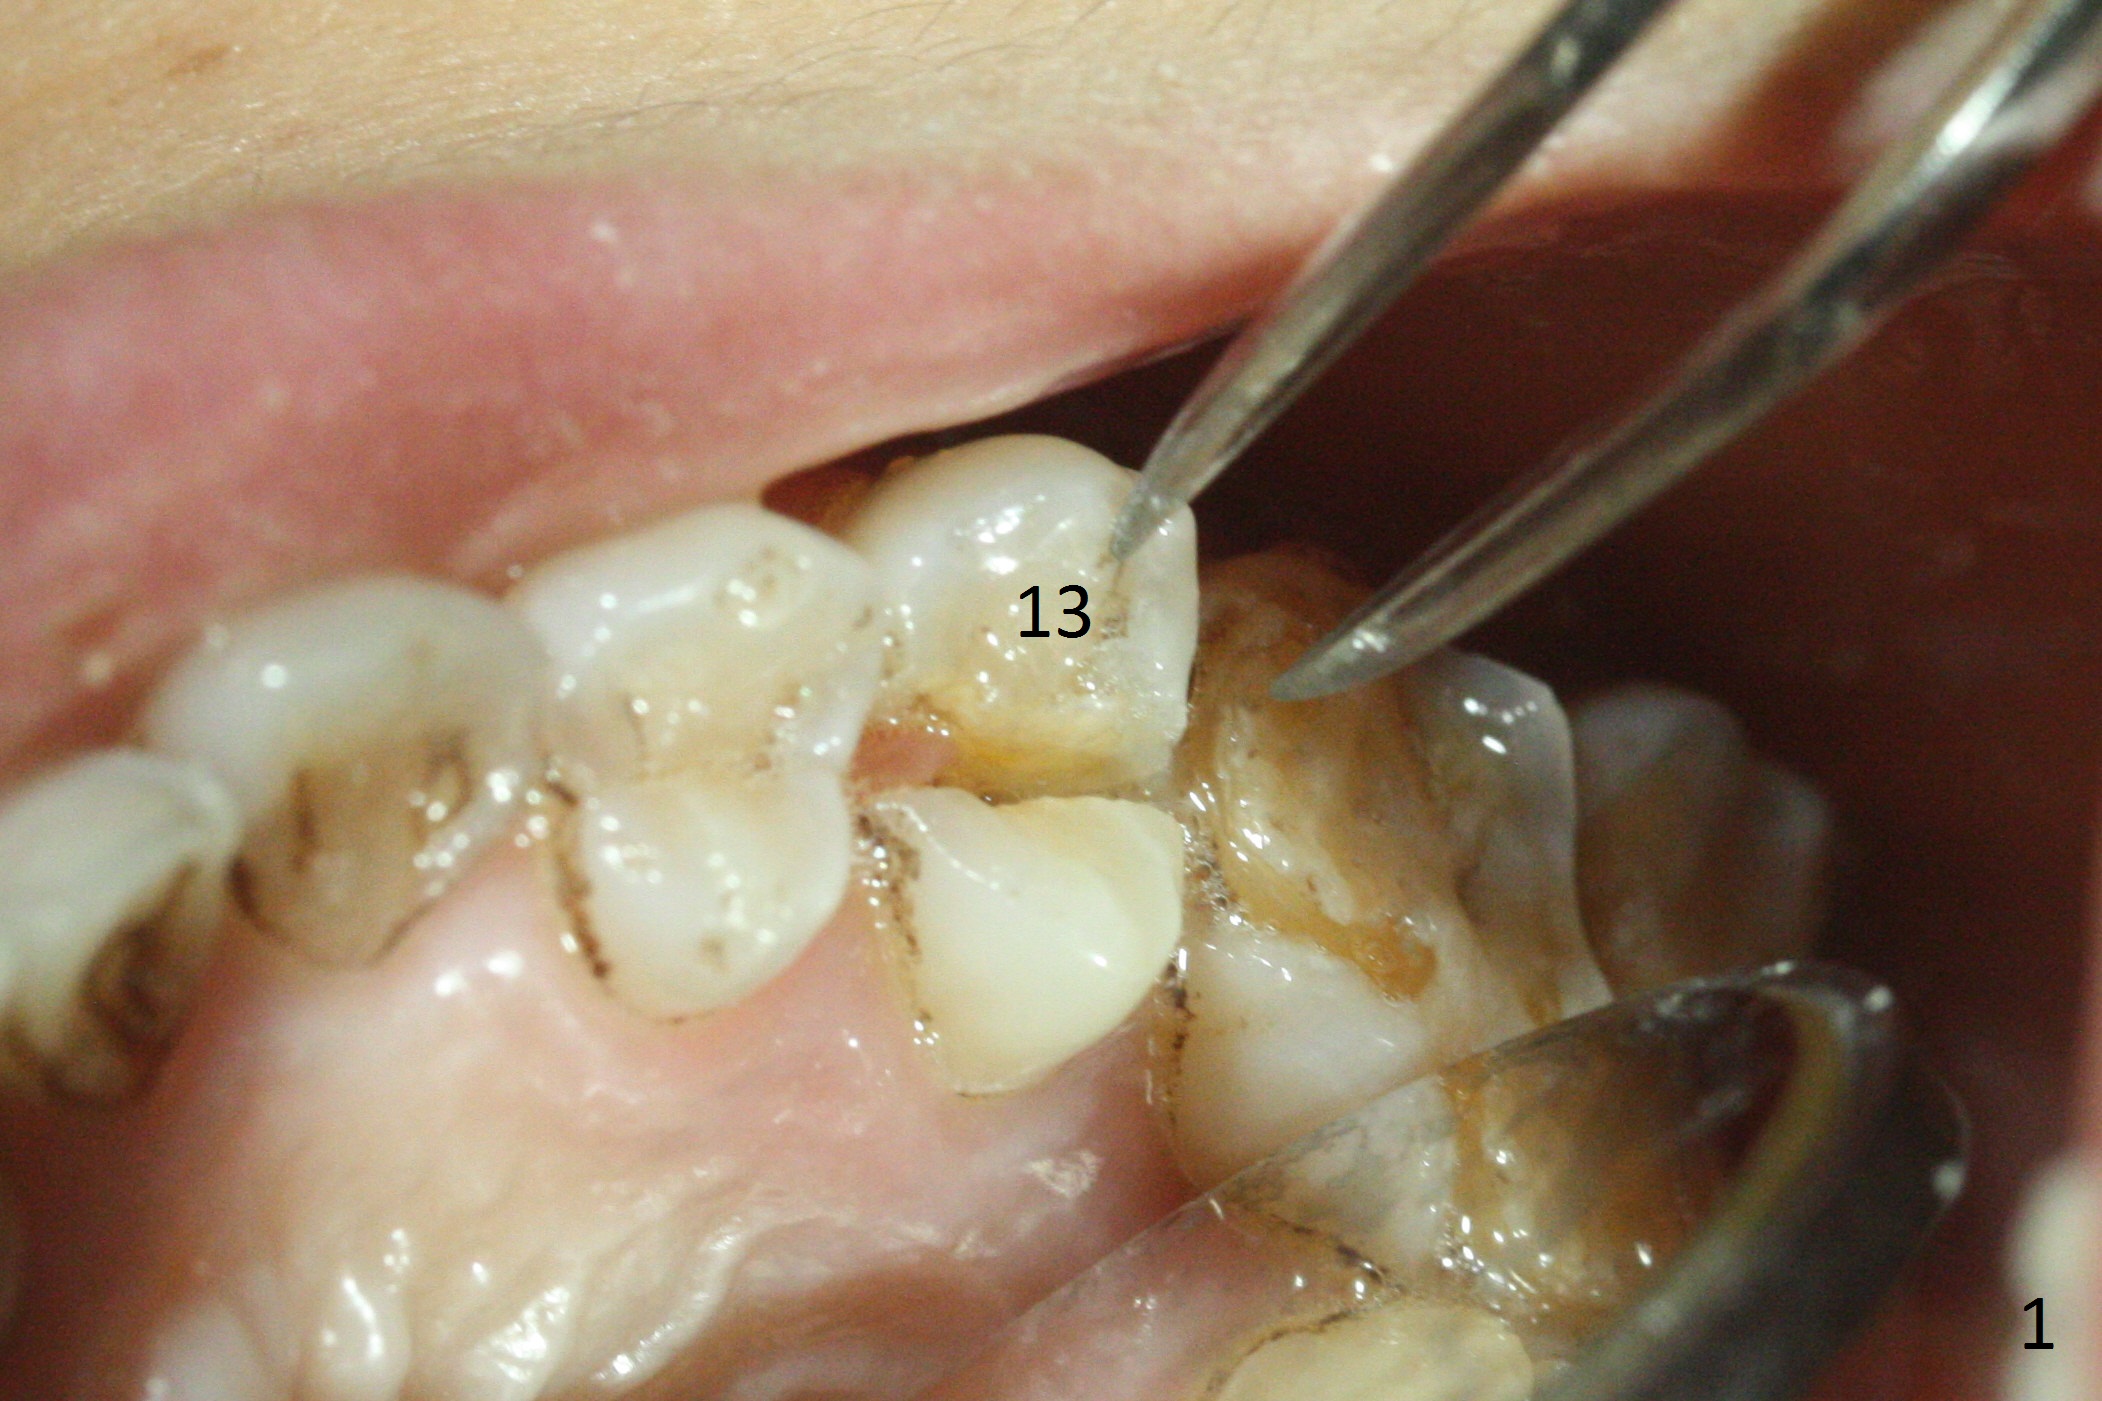

3.8 or 4.0x15 mm Implant

A 42-year-old woman presents to clinic with cc "top left tooth cracks upon biting on a small piece of stone". The buccal gingiva is tender, corresponding to the loose buccal segment of the tooth #13 (Fig.1). The crack may be secondary to severe wear of the 1st molar (Fig.1,2) in addition to deep slope of the affected tooth. A 4.5x15 mm IBS implant will be placed (Fig.3). Take PA following pilot drilling.